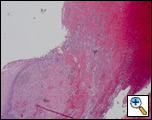

Figure 4: Histopathology reveals transmural acute and chronic inflammation with extensive ulceration and necrosis of the esophagus.

The patient made an uneventful postoperative recovery and was discharged from the hospital twelve days later. Surgical pathology demonstrated transmural acute and chronic inflammation with extensive ulceration and necrosis throughout the esophagus (Figure 4). Histology was negative for viral inclusions and malignancy. Microbiology revealed C. albicans from the mediastinal abscess.